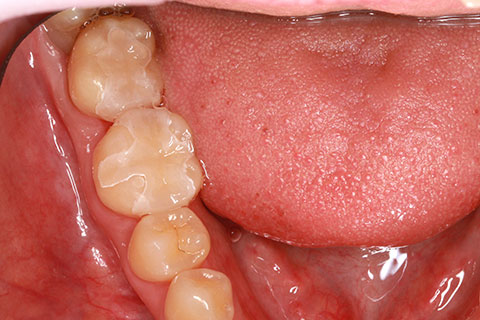

ジルコニアブリッジの症例1

- 年齢・性別

- 30歳男性

- 治療期間

- 1ヶ月

- 抜歯

- 右下5番欠損

- 治療費

- 16.5万円(税込み)

- 備考

- 歯質の削除量を最小限に抑えるブリッジ治療

- 治療内容

- 欠損部位の隣接歯を削合後、セメント合着

- 施術の副作用(リスク)

- 知覚過敏、歯髄炎、荷重負担